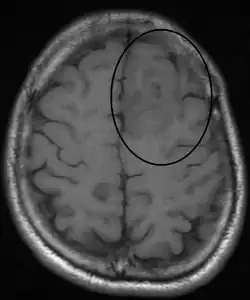

Oligodendroglioma arise mainly in the frontal lobe and in 50–80% of cases, the first symptom is the onset of seizure activity without any prior symptoms .[3] Headaches associated with increased intracranial pressure are also common in individuals with oligodendroglioma. Depending on the location of the tumor, many different neurological and neuropsychological deficits can be induced, including, but not limited to, visual loss, motor weakness, cognitive decline, and anxiety.[4] A computed tomography (CT) or magnetic resonance imaging (MRI) scan is necessary to characterize tumor size, location, and hetero- or homogeneity. Final diagnosis relies on biopsy and histopathologic examination of the tumor mass.[3]